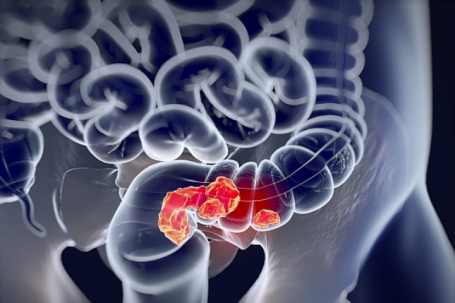

Loại cá dễ 'nuôi lớn' tế bào ung thư: Ngon miệng, đưa cơm nhưng người Việt không nên ăn nhiều Cá ướp muối tuy là món ngon, “gây nghiện” với nhiều người, nhưng lại tiềm ẩn nuôi lớn tế bào ung thư, mang lại nhiều rủi ro sức khỏe.